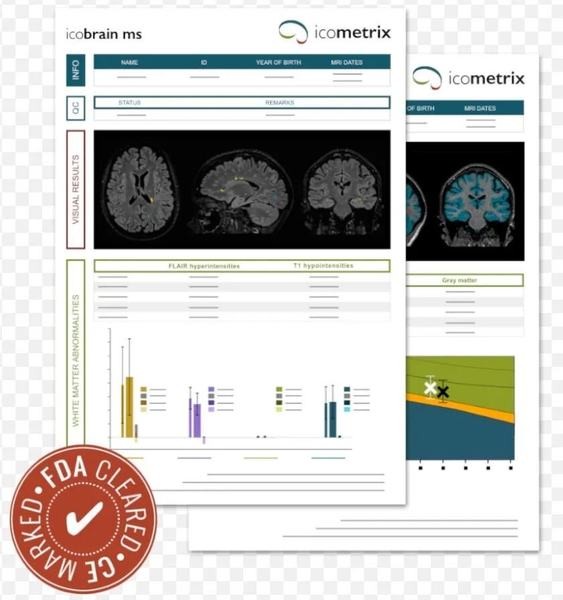

AI 脑部影像分析公司 Icometrix

项目类型

器械质押区

起投金额

1900USDT

每日释放:0.8

释放周期:40 天

已购: 63157

剩余: 0